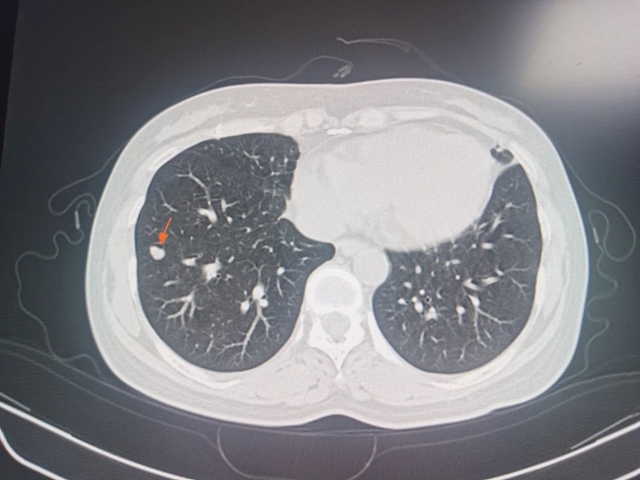

一年后复查,肝右前叶近肝缘小结节灶、肝右叶病灶内壁结节较前明显减小;但甲胎蛋白较前升高,通过胸部CT检查发现肺部两个实性结节,综合患者病情考虑肿瘤复发伴肺部转移,又为其实施了“CT引导下肝肿瘤肺转移灶微创消融术”,术后定期复查患者肝功能、甲胎蛋白均未见异常,病情稳定。

术前胸部CT